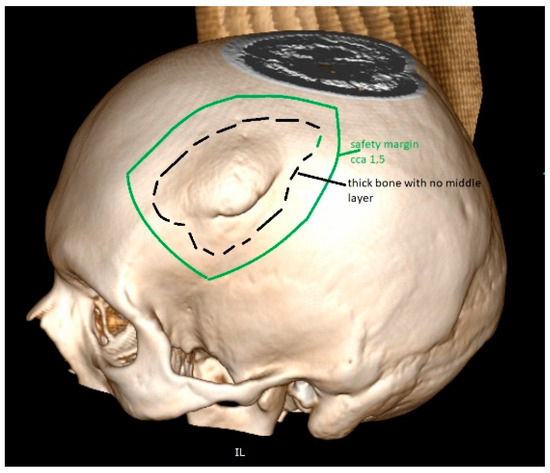

The artificial bone flaps made of titanium, PEEK and porcelain are custom-made in advance of the implantation. Before the operation, an accurate CT scan of the head is needed to manufacture a three-dimensional model for artificial flap manufacturing [83,84,85]. The CT scan is performed with 1 mm slices and with no gantry, ensuring that the flap, once produced, is completely compatible with the bone defect in the patient’s skull (Figure 6). One disadvantage is that the artificial bone flaps lack osteoinductive or osteogenic properties. Their production may take weeks before being delivered to the clinical department and it is not very available. Moreover, these products are very expensive and their production needs to be planned well in advance, according to the shape of the bone defect [72,77,81,82,83,84,85].

Figure 6. The tumour invades the cranial bone. This part will be removed during surgery. For the reconstruction, one alternative also includes PEEK, which is very popular for artificial flap manufacturing. The 3D reconstruction needs to be performed before the manufacturing of such PEEK implant. The safety margin of resection is included in the planning, providing enough space for diseased bone removal and proving a good fit.